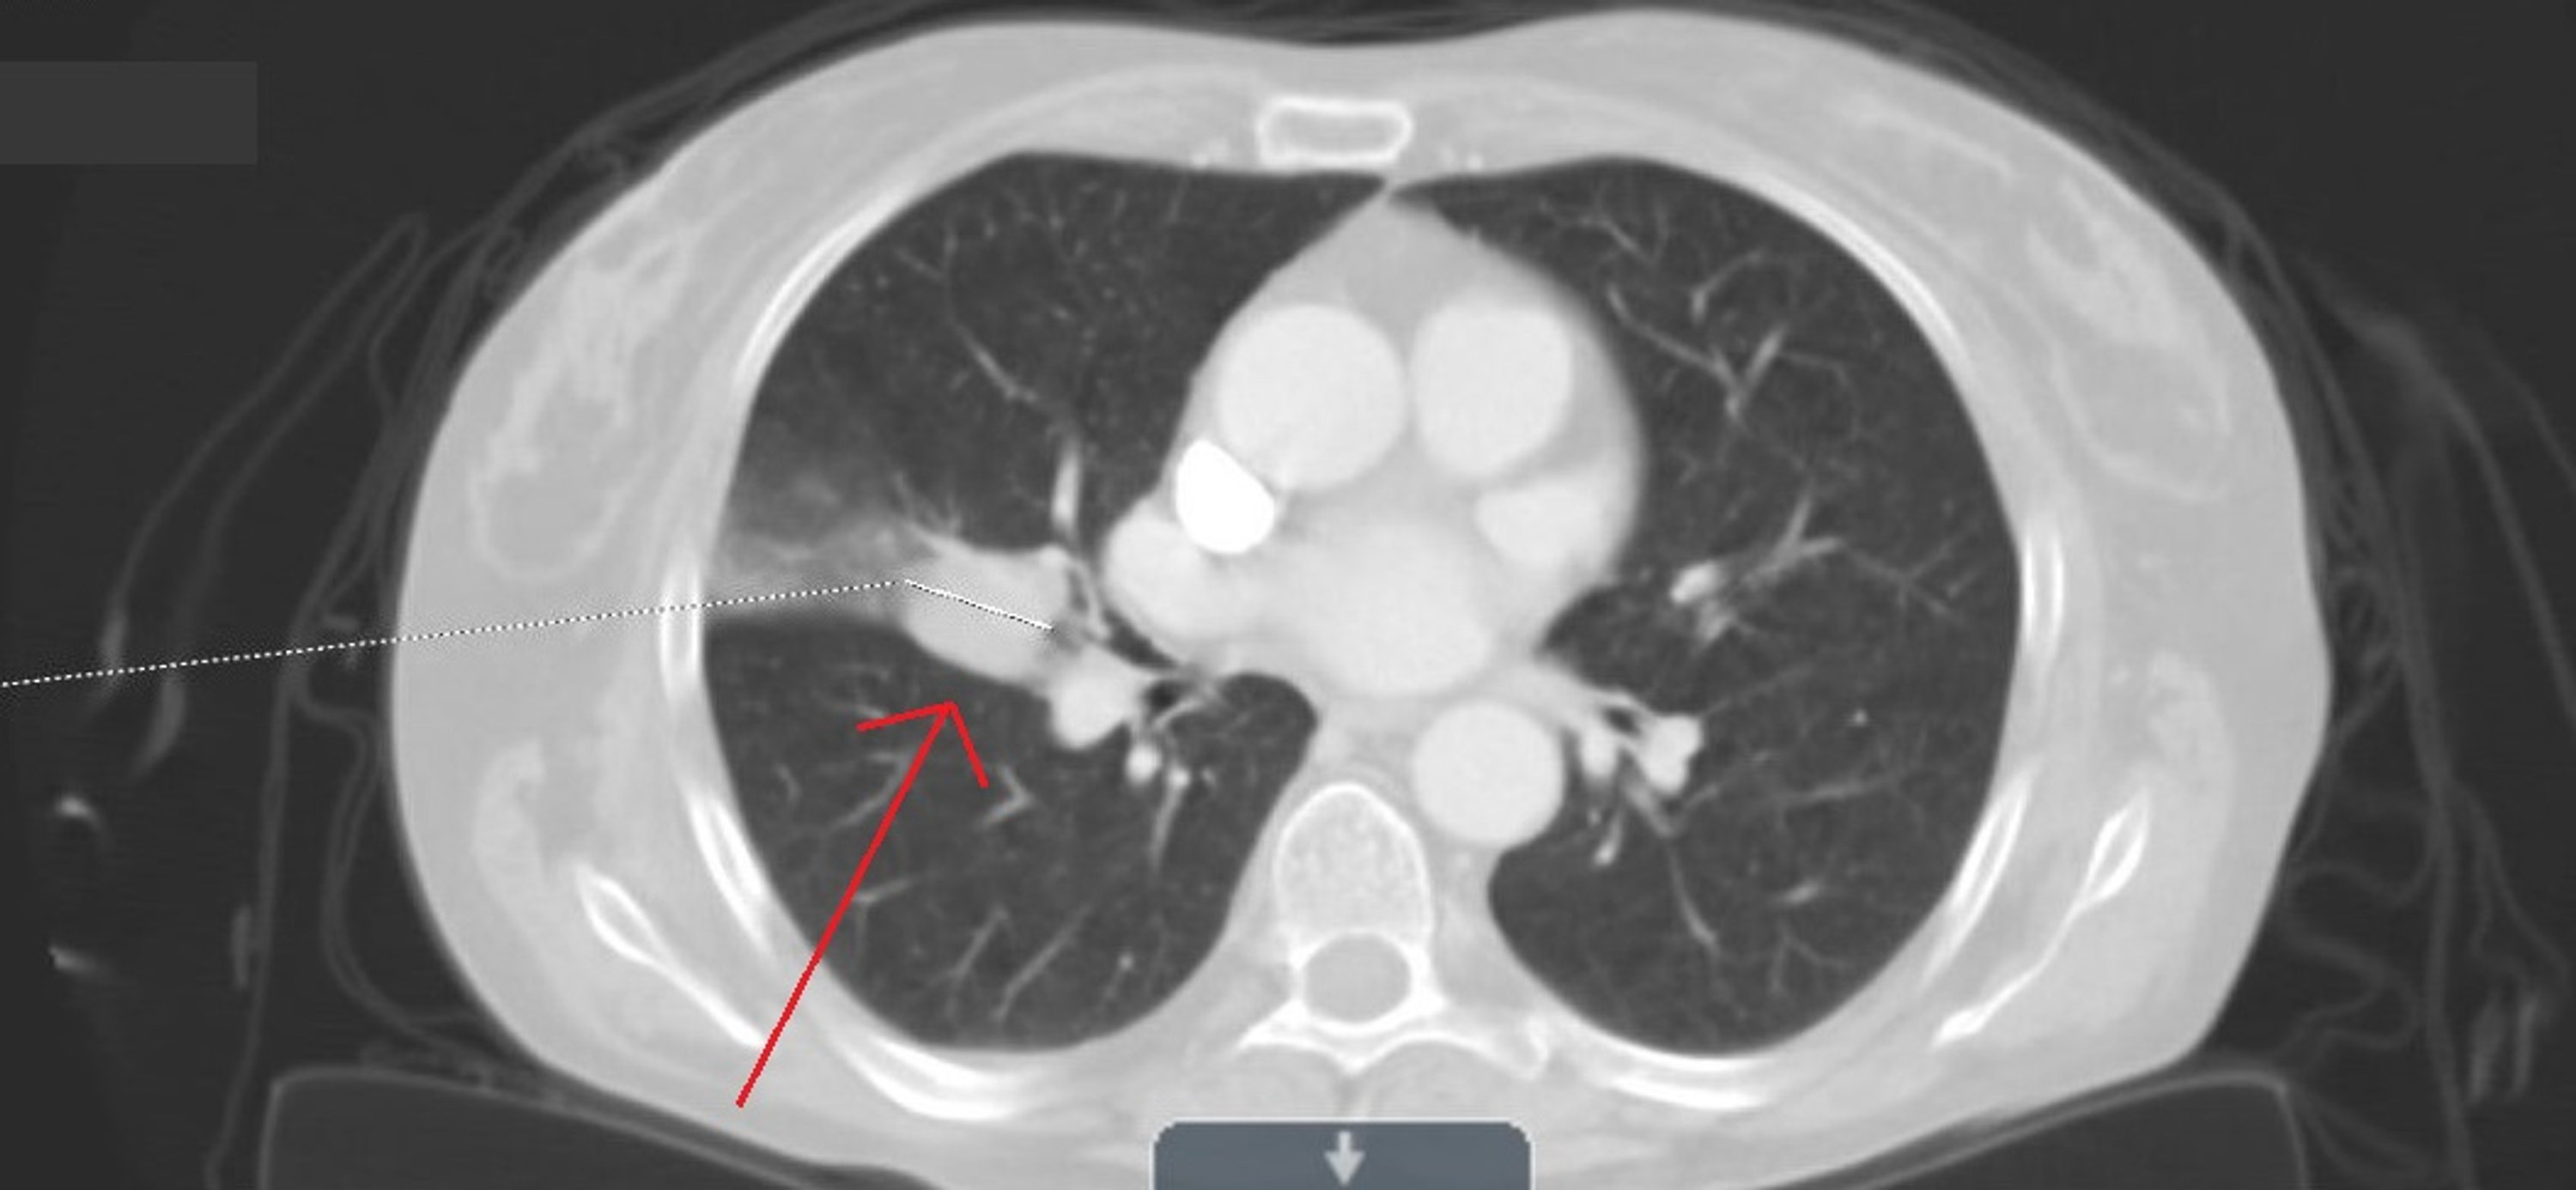

An overview of how asbestos exposure affects the lung The BMJ How Do You Tell If You Have Asbestos In Your Lungs — advanced asbestosis appears as excessive whiteness in your lung tissue. — asbestosis is a type of lung disease caused by breathing in asbestos dust and fibers. see a gp if: — tests to identify asbestosis and other forms of lung fibrosis look for key symptoms, such as strange breathing sounds, scar tissue in the. The. How Do You Tell If You Have Asbestos In Your Lungs.